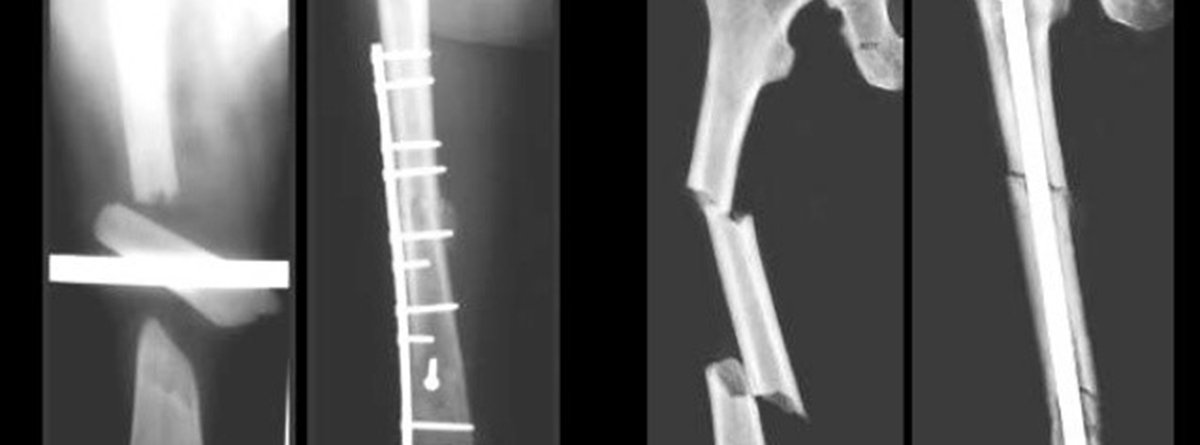

- Placas: fabricadas en titanio o acero inoxidable, se colocan sobre la superficie ósea y se aseguran con tornillos. Se utilizan sobre todo en fracturas de huesos largos.

- Clavos intramedulares: introducidos en la década de 1940, este tipo de material está diseñado para la colocación intramedular en huesos largos, tales como el fémur, la tibia o el húmero.

En estas imágenes vemos una fractura de fémur tratada con placa atornillada y otra con un clavo que va por dentro del hueso. Utilizar uno u otro sistema depende de la fractura.